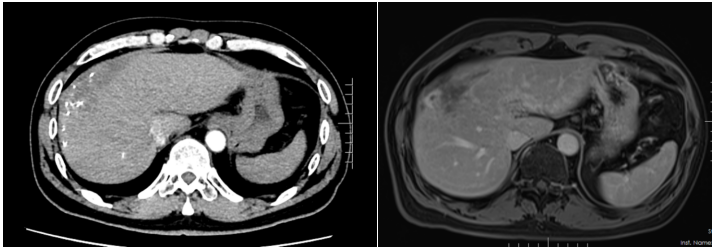

患者入院时诉说了自己与晚期肝癌对抗的痛苦与不易,同时也表明了与病魔抗争到底的决心。入院后,龙奎副主任医师立即为患者完善了CT、MRI+MRCP,ICG等检查,经过术前多学科MDT讨论后,认为患者肝癌转化效果满意,可以手术治疗。

由于患者肝癌位置特殊,肿瘤占据肝脏多个亚段,并且门静脉伴有海绵样变,手术中出血风险较大。另外,如大范围切肝,残余健全肝脏较少,术后有肝功能衰竭风险。为了保证患者手术质量安全,肝胆胰外科三病区高度重视,龙奎副主任医师组织科室详尽讨论了患者手术方案,在老专家孙敏教授、滕毅山教授、莫小华教授的鼎力支持下,最终决定采用腹腔镜微创手术方式完成手术,以最小的创伤让患者获得最大的收益。

手术中,由于患者有门静脉海绵样变特别容易出血,转化治疗后肝内管道走行变异,手术过程尤其艰难。龙奎副主任医师、董文志副主任医师、孙翊程医师与财神捕鱼 优秀的麻醉团队、手术室护士团队通力合作,利用财神捕鱼 先进的荧光腹腔镜导航辅助,精准地完成了腹腔镜下肝IVb段+V段+胆囊切除术,历时5个小时,出血量200ml。